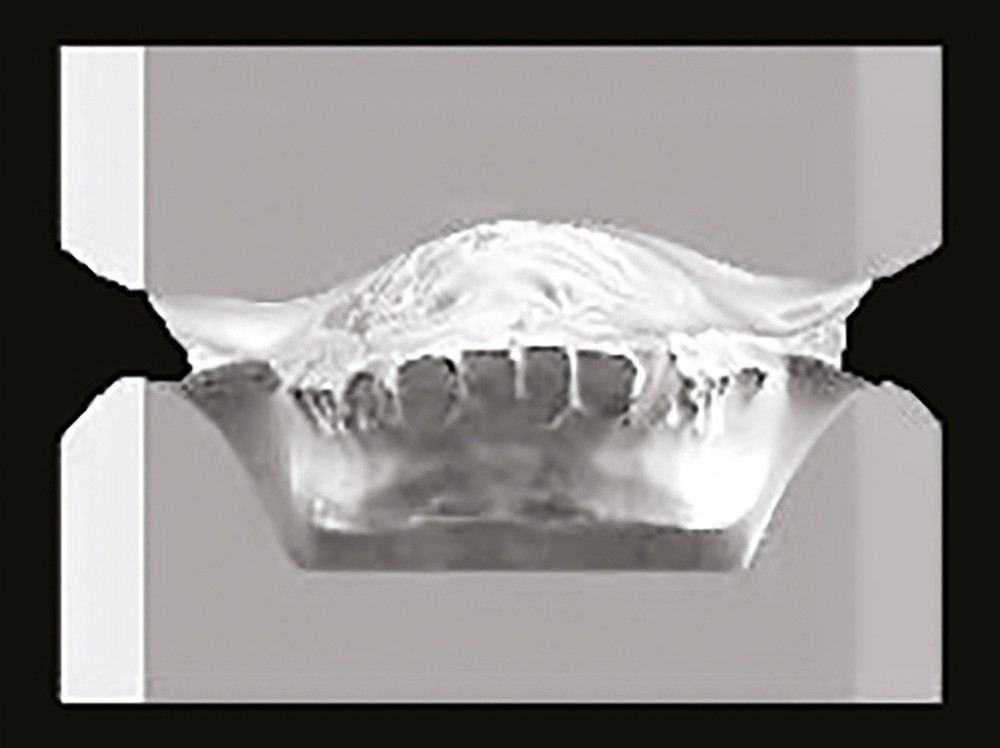

Son profil convexe s’inscrit dans un contexte de classe II squelettique par rétrognathie mandibulaire normodivergente sur un schéma de Classe II/2 avec supraclusion et encombrement modéré (fig. 1 à 7).

La formule dentaire est complète, avec un léger retard d’évolution des deuxièmes molaires (fig. 8).